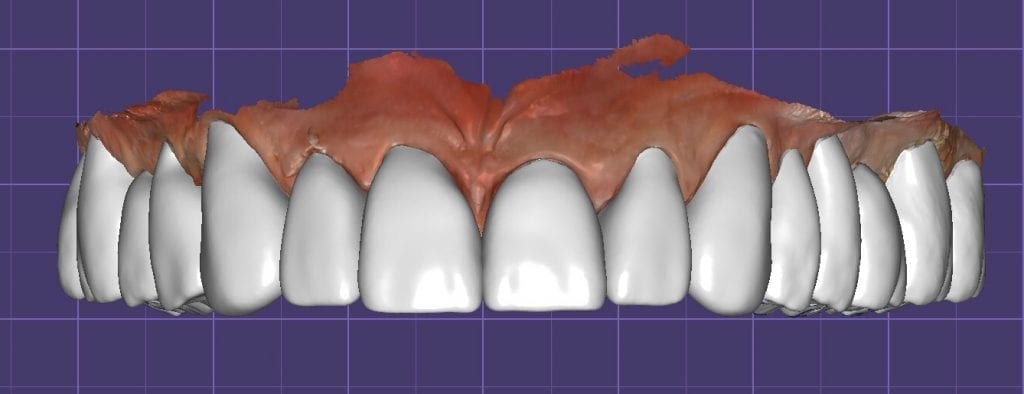

The digital models were then imported into a third party software where a library of tooth morphologies are available for the clinician to choose from.

Once the appropriate library is chosen, the digital wax ups are performed. In the subsequent photos you can see the transparent overlay of the wax-ups to the original position of the existing dentition